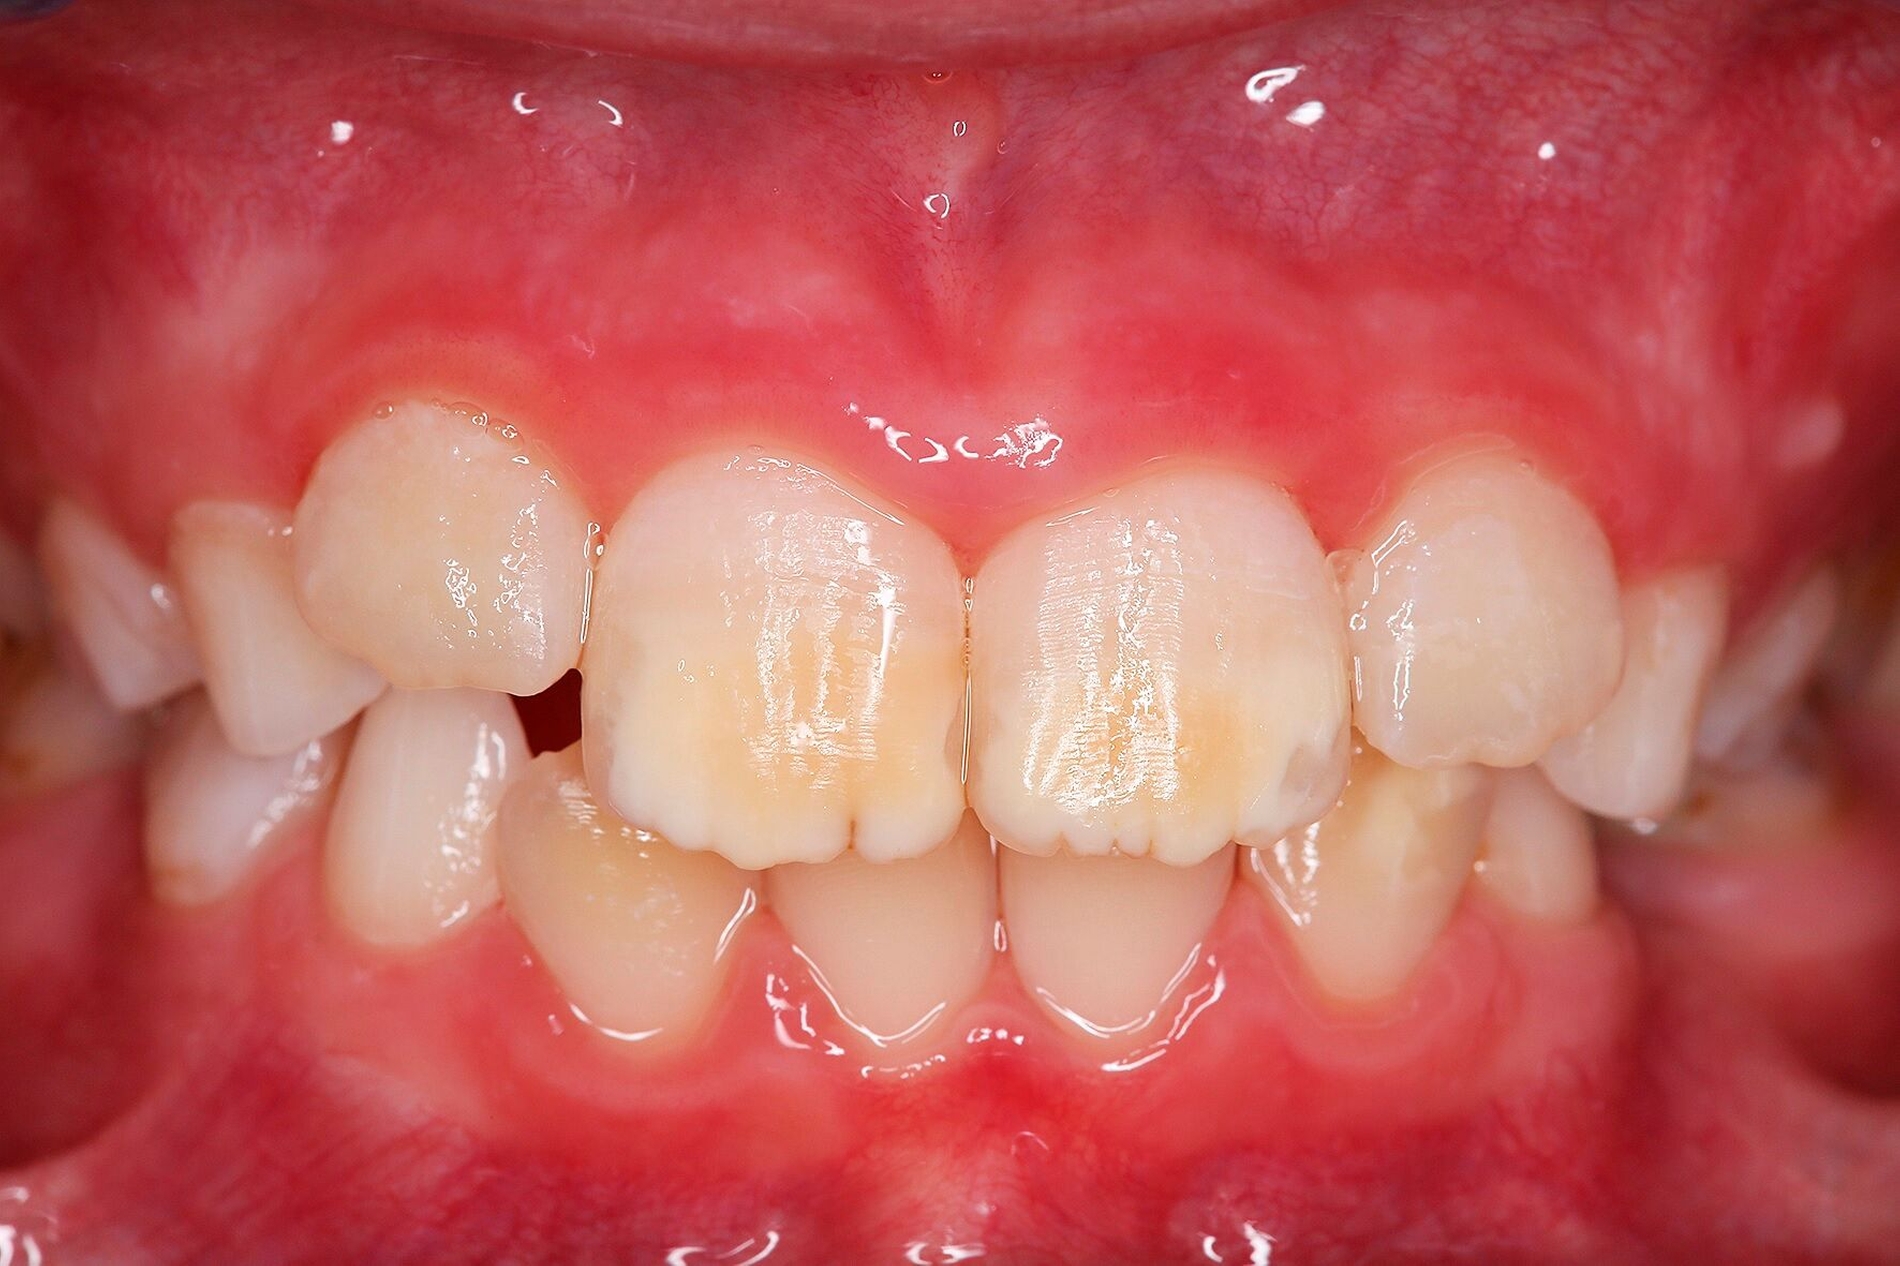

Der Begriff der „Molaren-Inzisiven-Hypomineralisation“ hat vor knapp 20 Jahren Eingang in die Literatur gefunden [Weerheijm et al., 2001]. Beschrieben wird eine systemisch bedingte Hypomineralisation von ein bis vier bleibenden ersten Molaren mit oder ohne Beteiligung der Inzisiven (Abbildungen 1 und 2).

Die Ausprägung der Mindermineralisation kann stark variieren (Abbildungen 3 und 4). Klinisch zeigen sich an den betroffenen Zähnen unterschiedlich starke Verfärbungen beziehungsweise Opazitäten bis hin zu ausgeprägten Schmelzverlusten. So kann die Mineralisationsstörung im Bereich der Molaren auf einzelne Bereiche beschränkt sein, das Fissurenrelief einbeziehen oder sich über die gesamte Glattfläche erstrecken [Koch et al., 1987]. Bei den Inzisiven ist die Mindermineralisation bukkal zu finden. Geringgradig betroffene Zähne sind dabei eher durch weiß-gelbliche oder gelb-braune, unregelmäßige Verfärbungen gekennzeichnet, schwere Hypomineralisationsformen weisen dagegen abgesplitterte oder fehlende Schmelz- und/oder Dentinareale unterschiedlichen Ausmaßes auf.